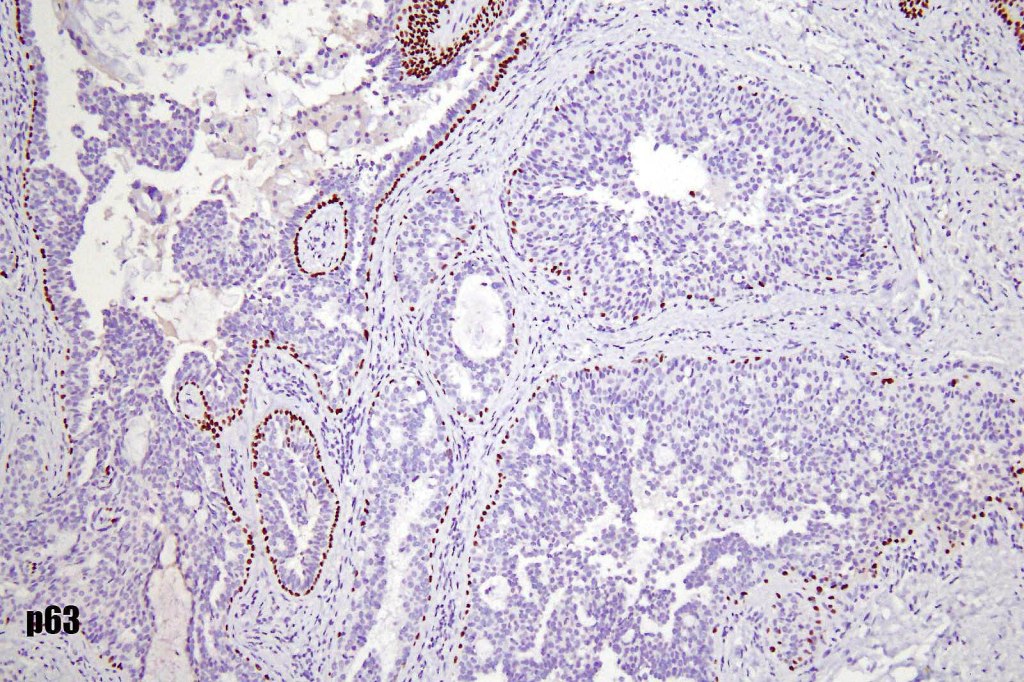

•Myoepithelial cells p63, SMA & calponin +ve

•EMPSGCa– multiple nodules of uniform epithelial cells with vesicular nuclei & small nucleoli

•In situ component sometimes evident

•Papillae & cribriform pattern sometimes evident